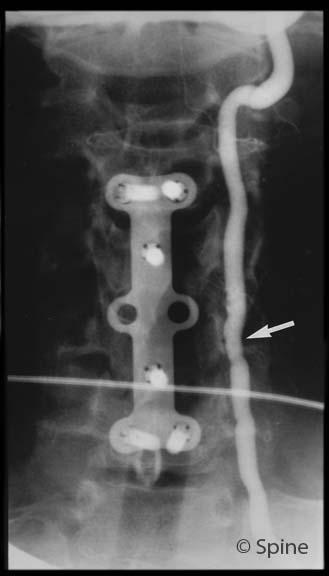

A post-op x-ray showing the instrumentation I devised to reattach the skull to the spine.